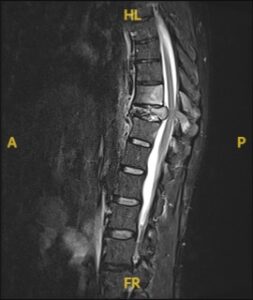

1. Pre-Surgical Evaluation: Includes imaging studies (MRI, CT, or X-rays), biopsy (if needed), and a thorough assessment of overall health.